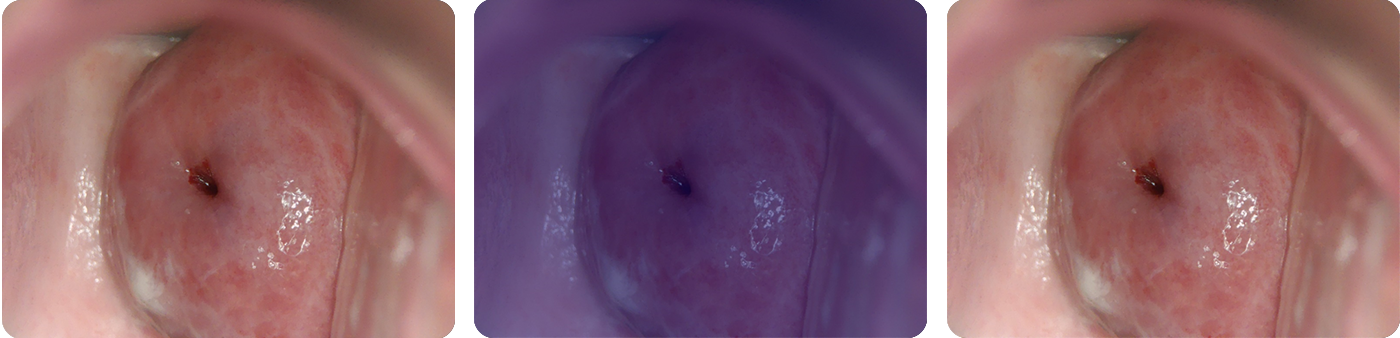

Cerviray AI

Normal

CIN1